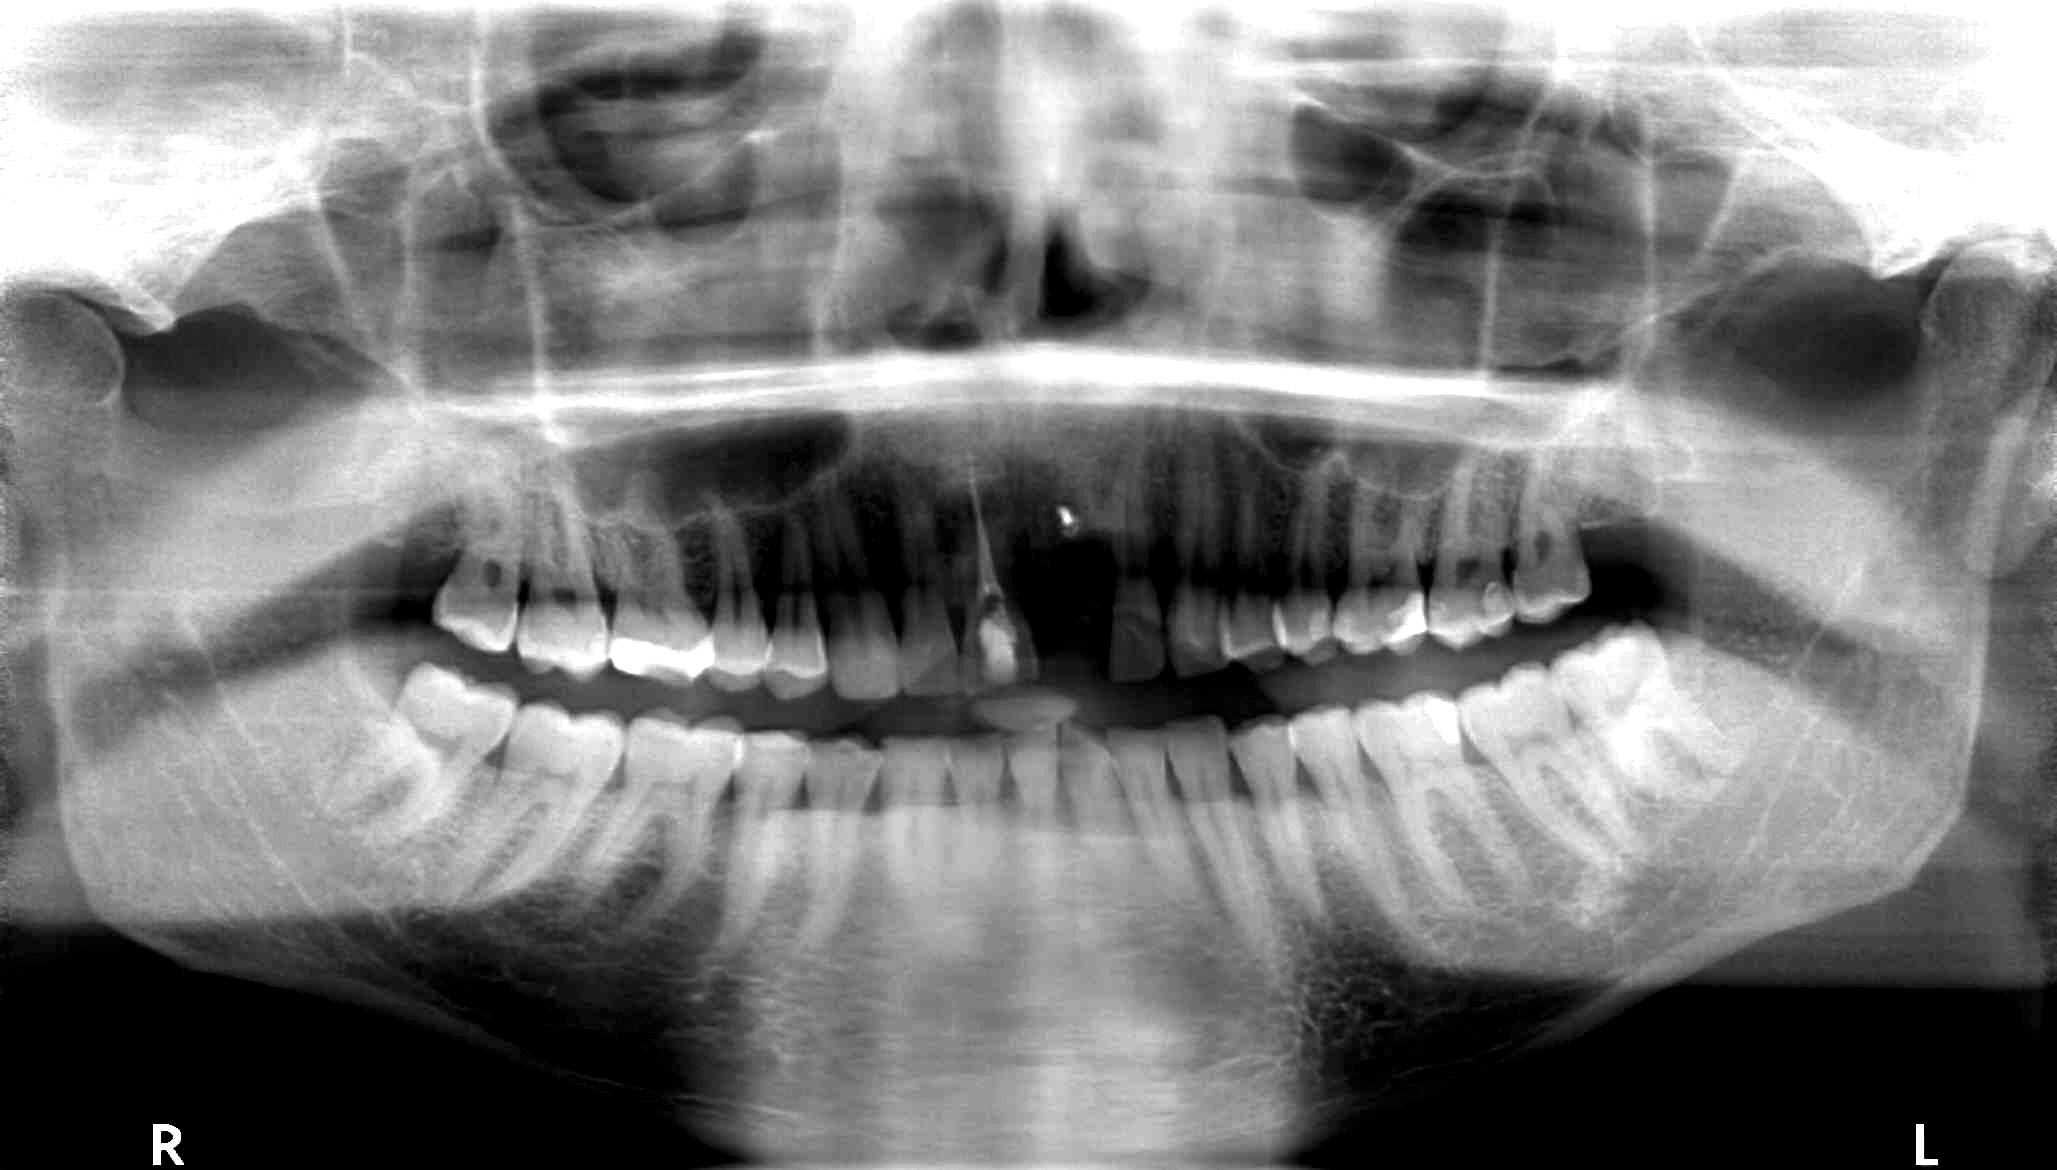

01/18 - Initial CBCT scan - Fracture of left maxillary incisor and loss of buccal wall